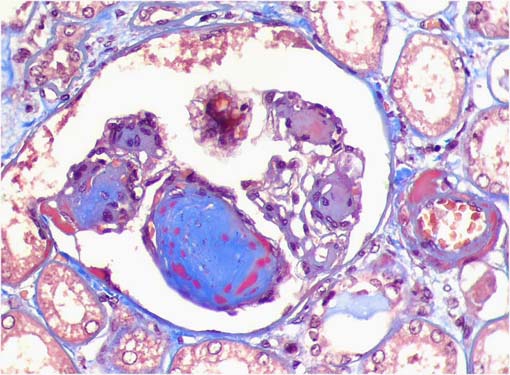

Figura 3.

Tricrómico de Masson, X400.